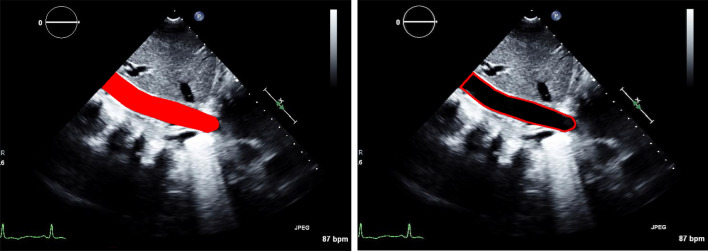

Our segmentation algorithm achieved excellent performance segmenting the IVC region with an IoU score of 0.96 ± 0.03 and a DSC score of 0.98 ± 0.05. In addition, our lightweight segmentation algorithm achieved an inference speed of > 60 frames per second (FPS). Figure 3 shows an example of the automatically segmented region along with the automatically generated contour.

Fig. 3.

Left: the automatically generated mask overlayed on the original image; right: the contour of the overlayed mask